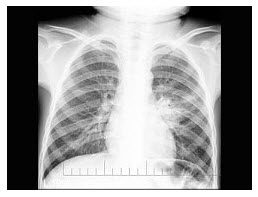

男,17岁,右腿酸痛、肿胀2个月余。右膝关节平片如下,最可能的诊断为()

A.纤维性骨皮质缺损